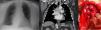

Se remite a neumología una mujer de 74 años por el hallazgo incidental de una masa mediastínica en una radiografía de tórax (fig. 1a). La paciente estaba asintomática y la exploración física no mostraba hallazgos de interés.

a) Imagen de la masa mediastínica en la radiografía de tórax. b) Imagen de la TC torácica en la que se visualiza la masa en mediastino medio. c) Imagen del paraganglioma durante la intervención quirúrgica en el centro de la imagen. La tráquea se sitúa en su parte superior y la vena innominada superior a esta. A la derecha se encuentra la arteria aorta y en la parte inferior el tronco arterial pulmonar.

Se realizó una TC torácica en la que se objetivó una masa hipervascularizada en mediastino medio de 48×43mm que desplazaba la tráquea, el esófago, la aorta ascendente y el hilio derecho (fig. 1b), por lo que se realizó el diagnóstico diferencial entre paraganglioma, enfermedad de Castleman, malformaciones vasculares y metástasis1.

Posteriormente, se realizó una gammagrafía con octreótido y un estudio funcional con los cuales se estableció el diagnóstico de paraganglioma no funcionante de mediastino medio y se decidió su resección quirúrgica mediante esternotomía media (fig. 1c) con embolización previa.